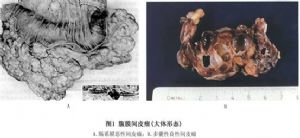

腹膜间皮瘤大体观察类似于胸膜间皮瘤,有2种类型,即弥漫性腹膜间皮瘤与局限性腹膜间皮瘤,一般说来,弥漫性间皮瘤75%为恶性,而局限性间皮瘤多为良性。前者瘤组织呈众多小结节或斑块被覆于腹膜的壁层或脏层,随着肿瘤的发展,则呈片块状的增厚,广泛铺盖于壁层腹膜或腹腔脏器的表面,可伴有大小不等的肿瘤或结节。肿瘤组织多呈灰白色,质地坚韧,亦可呈胶冻状,可有出血及坏死。瘤组织中,纤维组织增生,甚至有玻璃样变。瘤组织可侵入肝脏或肠管,但很少侵入脏器的深部,大网膜可完全被肿瘤组织所代替,肠管可发生粘连,腹腔内有渗出液,甚至血性腹水。在局限性腹膜间皮细胞瘤,瘤组织呈结节状或斑块状位于腹膜壁层或脏层,呈灰白色,质地较硬,界限清楚,很少出血及坏死(图1)。

腹膜间皮细胞瘤大体观察类似于胸膜间皮瘤,有2种类型,即弥漫性腹膜间皮细胞瘤与局限性腹膜间皮细胞瘤,一般说来,弥漫性间皮瘤75%为恶性,而局限性间皮瘤多为良性。前者瘤组织呈众多小结节或斑块被覆于腹膜的壁层或脏层,随着肿瘤的发展,则呈片块状的增厚,广泛铺盖于壁层腹膜或腹腔脏器的表面,可伴有大小不等的肿瘤或结节。肿瘤组织多呈灰白色,质地坚韧,亦可呈胶冻状,可有出血及坏死。瘤组织中,纤维组织增生,甚至有玻璃样变。瘤组织可侵入肝脏或肠管,但很少侵入脏器的深部,大网膜可完全被肿瘤组织所代替,肠管可发生粘连,腹腔内有渗出液,甚至血性腹水。在局限性腹膜间皮细胞瘤,瘤组织呈结节状或斑块状位于腹膜壁层或脏层,呈灰白色,质地较硬,界限清楚,很少出血及坏死(图1)。